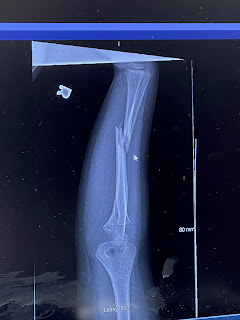

Dr. Huber showed me the post op x-ray and explained that Isaiah has small incisions at his wrist and elbow and a 3cm incision on his forearm where they cleared the muscle from between the bones and straightened the bone. He told me that Isaiah has a half cast right now--plaster on top, stabilized on the bottom and wrapped in ace bandage. In 2 weeks he will get a hard cast below his elbow which he will have about 4 weeks. And then he will have a removable brace. In 3-4 months the rods will be removed at a surgery center in a short, easy procedure. And then I waited for Isaiah to wake up enough for him to come back to me.